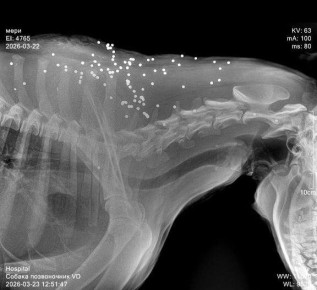

Напомним, на стрелков пожаловались жители Нижней Хобзы, где погибла бездомная собака и ещё несколько животных пострадали.